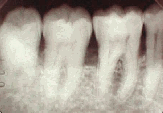

生えかたの違う親知らずのレントゲン写真を幾つかご覧に入れます。

ほぼ正常に生えている親知らず(一番左の歯)。これならばあまり問題は生じません。「第三大臼歯」として立派に機能します。通常のブラッシングをしていれば虫歯にもなりにくく、前の歯の状況次第ではブリッジに使う場合もあるので安易に抜歯はしません。